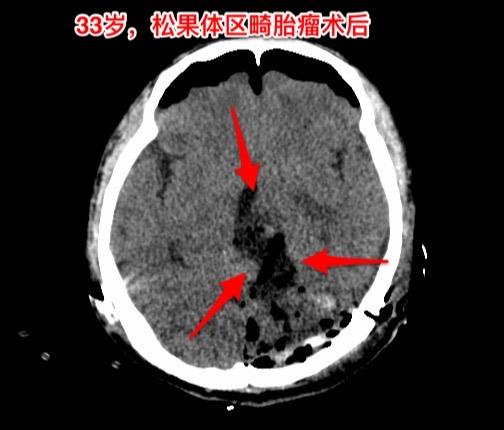

33岁贵州男性,脑部畸胎瘤。33岁贵州男性,病史11年。 11年前因多饮多尿在北京市某医院按生殖细胞瘤行全脑放疗,之后症状好转,能工作。 近两个月他记忆力差、爱睡觉、听力下降、视力下降。脑部磁共振显示松果体区肿瘤,在北京市某医院行肿瘤穿刺活检术,病理报告结果考虑是乳头型颅咽管瘤(活检标本标注为鞍区占位,可能误导了病理科医生,见图6)。 放疗医生及化疗医生说根据这个病理 结果是不敢实施放疗和化疗的。神经外科医生说开颅切除肿瘤风险非常大。 处于绝